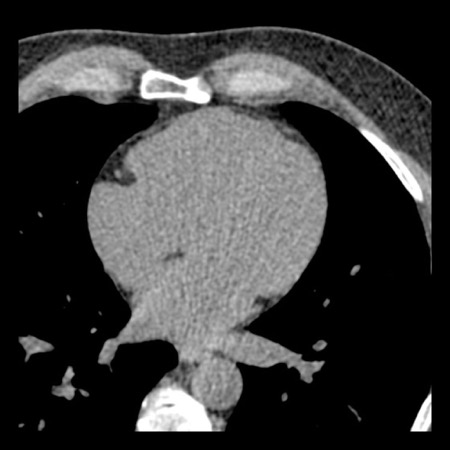

case 4 – CAD-RADS 3/P1/I+ thrombus left ventricle

First, scroll through the CTA images.

How would you describe the findings on the coronary CTA?

The findings are:

- Moderate (50-69%)

stenosis in the proximal LAD caused by a non-calcified plaque. - Variant of

sinoatrial (SA) nodal artery. The artery usually arises from the RCA as a second

branch after the conus artery, however in this case it arises from the LCX,

courses behind the aorta, anastomosing with the right atrium and with a small

branch supplies the SA-node of the heart. - Thrombus in the

apex of the left ventricle. - CTP was performed

in this patient. CTP showed a perfusion defect at stress imaging in the

territory of the LAD (I+), at rest no perfusion defect was visible.

This patient classifies as CAD-RADS 3/P1/I+, which means

this patient requires further investigation.